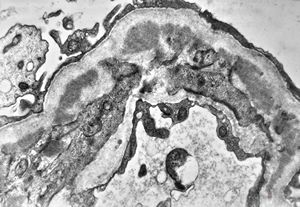

M,6y. | Alport syndrome- digital photo from the screen